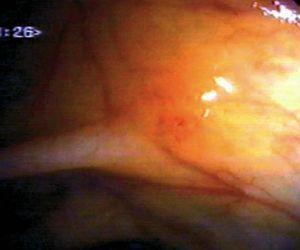

Fig. 3. Examples of flat lesions with conventional examination and after the application of indigo carmine 0.2-0.5%. a, b) Small flat adenoma, 3 mm in size. c, d) Large flat adenoma, 15 mm in size. e, f) Completely flat lesion (IIb in the Japanese classification). g, h) Depressed lesion, 3 mm in size) (IIc in the Japanese classification). I, J) Depressed lesion, 7 mm in size, histopathological study revealed submucosally invasive cancer (traditionally IIc in the Japanese classification, although recently such depressed lesions with a distinct central protrusion indicating submucosal invasion are termed IIc + Is). k, l) Flat elevated lesion with central depression, 10 mm in size, corresponding to a submucosally invasive cancer (IIa + IIc in the Japanese classification).